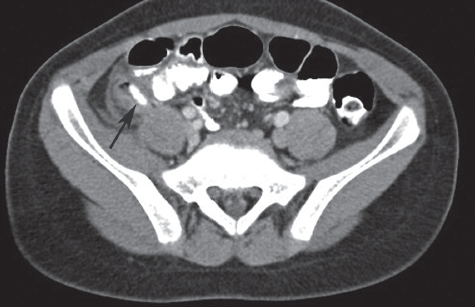

David Effron, MD; Maya C. Myslenski, MD

An 8-year old previously healthy boy presents to your office with a poor appetite, nausea, vomiting, and intermittent abdominal pain.